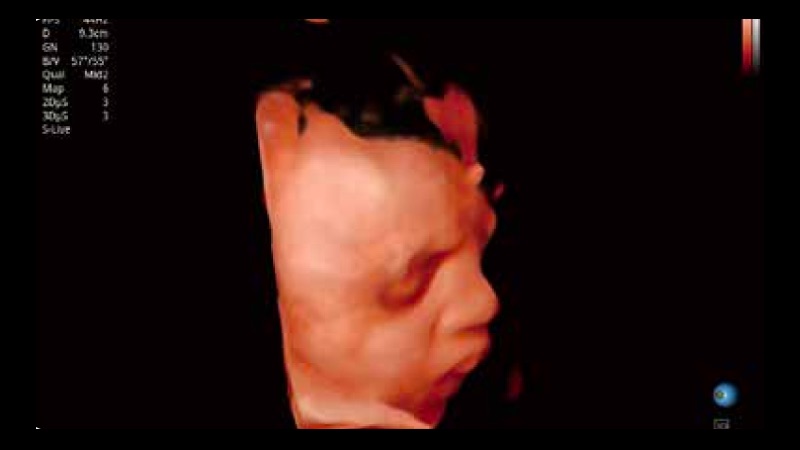

容积探头

凭借开立医疗先进的成像技术和优异的探头技术提供的清晰的图像表现,您可以更自信地做出临床决策。